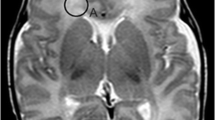

Before 18 weeks GA, laminar organization appeared blurred on 3.0T MRI (Figs. 2a and 3a), while after 18 weeks GA, it gradually appeared clearer (Figs. 4, 5, and 6). In delineating the lamination, on 3.0T MRI, T1-weighted images had higher image contrast than T2-weighted images (Fig. 4), while on 7.0T MRI, T2-weighted images had higher image contrast (Fig. 2b, c). On T2-weighted 7.0T MRI, the marginal zone (7 in Fig. 2b) could be observed.

Transverse T1-weighted (a) 3.0T MRI, and transverse T2-weighted (b) and T1-weighted (c) 7.0T MRI of 14 weeks GA. Three layers can be observed on T1-weighted 3.0T MRI. They are the ventricular zone (1), the intermediate zone (4), and the cortical plate (6). On 7.0T MRI, four layers including the marginal zone (7) can be observed, and the T2-weighted image (b) has higher image contrast than T1-weighted image (c)

Transverse T1-weighted (a) 3.0T MRI and T2-weighted (b) 7.0T MRI of 16 weeks GA. Three layers can be observed on T1-weighted 3.0T MRI, they are the ventricular zone (1), the cortical plate (6), and the layer with low signal intensity between the two zones above-mentioned, containing the periventricular zone (2), the subventricular zone (3), the intermediate zone (4), and the subplate zone (5). On T2-weighted 7.0T MRI, six layers can be observed. The marginal zone cannot be visualized because of the high signal emitted by the cerebrospinal fluid. From this GA on, the external capsule (white single arrow), which separates the intermediate zone and the subplate zone, can be clearly observed. The black single arrow shows that the lower part of the subplate zone is of low signal intensity on T2-weighted image at this GA

Sagittal (a), coronal (b) T1-weighted, and coronal T2-weighted (c) 3.0T MRI of 18 weeks GA. The layers appear typical at this GA, six layers including the continuing periventricular zone (2) and external capsule fibers (white single arrow) can be observed. The image contrast of T2-weighted image is inferior to that of T1-weighted image and only four layers can be distinguished. The borderline between the subventricular (3) and intermediate zone (4) cannot be delineated. The black single arrow shows that the lower part of the subplate zone is of high signal intensity on T1-weighted image at this GA

Coronal T1-weighted (a) 3.0T MRI, and coronal T2-weighted 7.0T MRI (b) of 20 weeks GA. Layers appear almost the same as that at 18 weeks GA on 3.0T MRI. On 7.0T MRI, seven layers including the marginal zone (7) can be observed. The borderline between the subventricular (3) and intermediate zone (4) can also be distinguished. The external capsule (white single arrow) still appears continuous, and the layer of high signal intensity (black single arrow in a) still appears at the lower part of the subplate zone on T1-weighted image at this GA

Coronal T1-weighted 3.0T MRI of 22 (a), 24(b), 26(c), 28(d), 30(e), 37(f) weeks GA. At 22 weeks GA, six layers can be observed but the periventricular zone (2 in a) and external capsule fibers region (white single arrow in a) appears discontinuous. After this GA, the external capsule (white single arrow in b–d) can only be discriminated at the region near the basal ganglia. The high signal layer (black single arrow in a), probably the migrating thalamocortical afferents, is now in the middle of the subplate zone (5 in a). Then, it migrates to the upper part of the subplate zone (5 in b–d) and mixes together with the cortical plate (6 in a–f, black single arrow in b–d). At 24–28 weeks GA, the lamination appears untypical, and the subplate zone appears wide. At 30–37 GA, the lamination almost disappears, and only remnants of the subplate zone (white single arrow in e, f) can be observed in the temporal lobe or the gyral crest. The periventricular fibers crossroads (white double arrows in d–f) can be clearly visualized after 28 weeks GA

The ventricular zone

This zone appeared as a low signal layer on T2-weighted images, but as a high signal layer on T1-weighted images. The layer could be visualized at 14 weeks GA (1 in Fig. 2), and at 16 weeks GA, it appeared as a wide low signal layer (1 in Fig. 3b) mixed with the periventricular zone (2 in Fig. 3b) above it. The ventricular zone, whose thickness appeared thinner as GA increased, was delineated as a typical layer linking the germinal matrix and encircling the lateral cerebral ventricle at 18–23 weeks GA (1 in Figs. 4, 5, and 6a). Borderlines between it and the layer nearby appeared distinct because the signal intensity of the ventricular zone was different from that of the periventricular zone (2 in Figs. 3, 4, 5, and 6a) above it and that of the cerebrospinal fluid below it. It was still visible until 37 weeks GA (1 in Fig. 6f).

The periventricular zone

This zone was delineated as a high signal layer on T2-weighted images, but as a low signal layer on T1-weighted images. The zone was visible at 15 weeks GA (2 in Fig. 3b). During 18–20 weeks GA, it appeared as a continuous layer (2 in Figs. 4 and 5) encircling the ventricular zone of high signal intensity, with clear borderlines between it and the layers nearby. It appeared discontinuous on 3.0T MRI at 22 weeks GA (2 in Fig. 6a). At 28 weeks GA, punctiform regions with low signal intensity stood out at the location where the previous periventricular zone had been. They were the periventricular fibers crossroads, which appeared apparent as GA increased (white double arrows in Fig. 6d–f).

The subventricular and intermediate zones

The subventricular zone appeared as a low signal layer on T2-weighted images and as a high signal layer on T1-weighted images. It was visible at 16 weeks GA (3 in Fig. 3b). At 18 weeks GA, mixed with the intermediate zone (3/4 in Fig. 4), it appeared as a high signal layer above the periventricular zone. But, most of it disappeared at 22 weeks GA (3/4 in Fig. 6a) and could not be visualized at 26 weeks GA (3/4 in Fig. 6c). A borderline between the subventricular and intermediate zones could not be delineated on 3.0T postmortem MRI during all developmental stages, but it could be observed in the occipital part of the brain on 7.0T MRI at 16 and 20 weeks GA (3 and 4 in Figs. 3b and 5b).

The intermediate zone, being visualized at 14 weeks GA (4 in Fig. 2), appeared as a wide layer with high signal on T2-weighted images (4 in Fig. 2b). The layers with low signal intensities above and below it were recognized as the pre-cortical plate and ventricular zone, respectively. At 16 weeks GA, the zone appeared apparent (4 in Fig. 3), with the bilateral sides forwardly linking the bottom part of the external capsule (white single arrow in Figs. 3, 4, 5, and 6d) and upwardly linking the inferior part of the subplate (5 in Figs. 3, 4, 5, and 6). The intermediate zone appeared wide and typical at 18–22 weeks GA (3/4 in Figs. 4, 5, and 6a), but after 24 weeks GA, it was hard to discriminate from the subplate zone above it. It eventually differentiated into fetal white matter (4 in Fig. 6d–f).

At 16–23 weeks GA, the external capsule fibers region (white single arrow in Figs. 3, 4, 5, and 6a), lying parallel to the periventricular zone with similar signal intensity, could be clearly delineated just above the intermediate zone, separating it from the subplate. This zone appeared discontinuous at 22 weeks GA (white single arrow in Fig. 6a) and could not be recognized at the parieto-occipital part of the brain at 24 weeks GA. But, it remained visible at the region near the basal ganglia (white single arrow in Fig. 6b–d).

The subplate zone

The signal intensity of this layer did not appear the same, appearing as a low signal layer on T2-weighted images and a high signal layer on T1-weighted images. The layer was visible at 15 weeks GA, as two adjoining layers of different signal intensities (5 in Fig. 3b) lying just below the cortical plate (6 in Figs. 2, 3, 4, 5, and 6). The subplate appeared wide at 18–20 weeks GA, containing two layers with different signal intensities (5 in Figs. 4 and 5), and it appeared much wider at 22–24 weeks GA (5 in Fig. 6a, b). The signal intensity of the subplate zone began to increase at 26 weeks GA (5 in Fig. 6c). At 28 weeks GA, it mixed with the cortical plate, a high signal layer, above it (5 in Fig. 6d). The subplate zone turned into punctiform regions and began to dissolve at 30 weeks GA (5 in Fig. 6e). At 37 weeks GA, only narrow layers of low signals, which were the remnants of the subplate zone (white single arrow in Fig. 6e, f), could be visualized in the temporal lobe or the gyral crest of the parieto-occipital part of brain, which constantly remained distinct during the last trimester because of its late disappearance.

Changes of signal intensities in the subplate zone could be visualized. On T1-weighted images at 16–20 weeks GA, the inferior part of the subplate zone had high signal intensity (black single arrow in Figs. 4a, b and 5a) while the superior part had low signal intensity. But, at 22 weeks GA, there was a high signal layer in the middle part of the subplate zone (black single arrow in Fig. 6a). And during 24–26 weeks GA, the high signal layer gradually migrated to the superior part of the subplate zone and got close to the cortical plate, where it mixed with the cortical plate, a high signal layer, at the parieto-occipital part of brain at 28 weeks GA (black single arrow in Fig. 6b–d). This moving high signal layer probably was the thalamocortical afferents migrating to the cortical plate.

The borderline between the subplate zone and the cortical plate above it could be clearly distinguished because of different signal intensities of the two. But, it appeared obscured at 26–28 weeks GA when the thalamocortical afferents migrated to the superior part of the subplate zone (Fig. 6c, d). At 30–37 weeks GA, the borderline between the cortical plate and remnants of the subplate zone (white single arrow in Fig. 6e, f) remained distinct at the temporal lobe.

The cortical plate

The signal intensity of this layer, different from that of the subplate, remained the same during developmental stages (6 in Figs. 2, 3, 4, 5, and 6). The cortical plate was located exterior to the subplate zone. After 28 weeks GA, it transformed into most of the gray matter.

The marginal zone

On T2-weighted 7.0T MRI at 14 and 20 weeks GA, the marginal zone could be visualized as a high signal layer exterior to the cortical plate at the frontal, occipital lobe, and regions near the hippocampus (6 in Figs. 2b and 5b). It could also be vaguely delineated on T1-weighted 7.0T MRI at 14 weeks GA (7 in Fig. 2c).